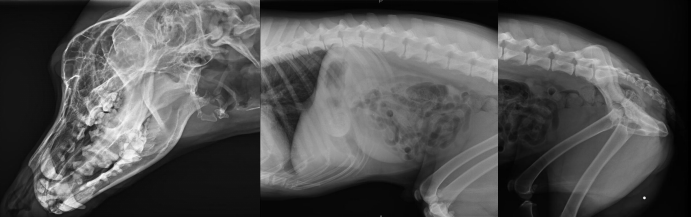

不管是人还是动物,有一项检查是非常常见的,就是X光拍片检查,X光检查是传统的影像学检查手段,它是应用较早、普遍,价格也相对便宜。主要用于一些疾病的初步检查,便于发现较明显病变的组织和结构,是疾病初筛优选的检查方式。那么,一般宠物拍X光片和人拍X光片有什么不同点,参数选择一样吗?